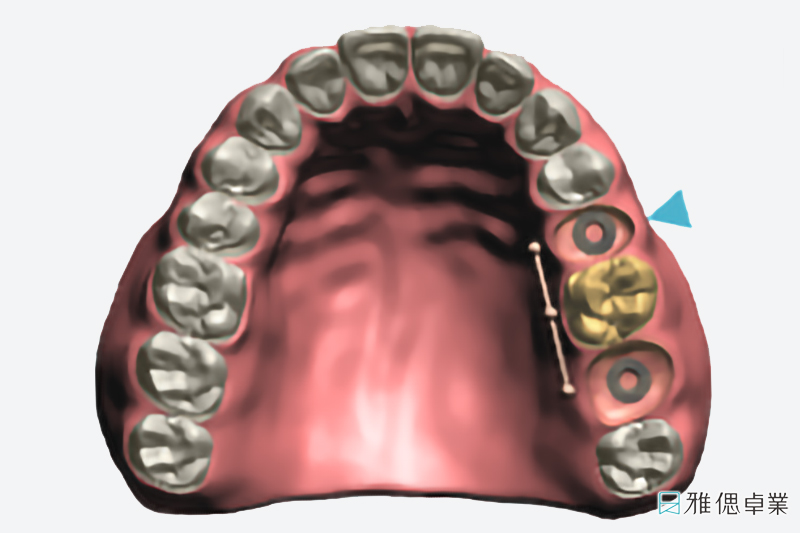

數位植牙是藉由影像導引(Imaging Guide)的技術保留手術導引(Surgical Guide)與電腦導航(Navigation)技術的優點,讓牙醫師在進行植牙手術時,清楚知道鑽孔的軸向與位置,即時改變或修正植牙手術計劃。

在植牙療程的過程中,專業醫師會透過「植牙規劃軟體」找出合適的植體大小及植入位置、角度與深度,再為患者設計專屬「手術引導板」,將手術引導板安裝在於患者的缺牙位置,定位適當的角度、位置與深度,快速完成高效能數位植牙療程、大幅提升植牙治療的舒適體驗!

植牙手術導引板設計過程